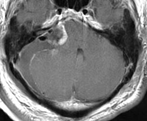

以下の画像に呈示するような脳幹や小脳を圧迫する大きい腫瘍に対しては、開頭手術が優先されます。手術中に神経刺激装置・聴性脳幹反応など電気生理学的モニタリングを併用し、1つ1つの手術操作によって神経機能を損傷していないか随時チェックしながら手術を行っており、術後後遺症の予防に努めています。